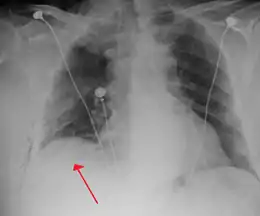

Chest X-ray

A plain chest radiograph, ideally with the X-ray beams being projected from the back (posteroanterior, or "PA"), and during maximal inspiration (holding one's breath), is the most appropriate first investigation.[30] It is not believed that routinely taking images during expiration would confer any benefit.[31] Still, they may be useful in the detection of a pneumothorax when clinical suspicion is high but yet an inspiratory radiograph appears normal.[32] Also, if the PA X-ray does not show a pneumothorax but there is a strong suspicion of one, lateral X-rays (with beams projecting from the side) may be performed, but this is not routine practice.[15][19]

Anteroposterior inspired X-ray, showing subtle left-sided pneumothorax caused by port insertion

Lateral inspired X-ray at the same time, more clearly showing the pneumothorax posteriorly in this case

Anteroposterior expired X-ray at the same time, more clearly showing the pneumothorax in this case

Chest X-ray showing a pneumothorax on the right (left in the image), where the absence of lung markings indicates that there is free air inside the chest

Chest X-ray showing the features of pneumothorax on the left side of the person (right in image)

It is not unusual for the mediastinum (the structure between the lungs that contains the heart, great blood vessels, and large airways) to be shifted away from the affected lung due to the pressure differences. This is not equivalent to a tension pneumothorax, which is determined mainly by the constellation of symptoms, hypoxia, and shock.[13]

The size of the pneumothorax (i.e. the volume of air in the pleural space) can be determined with a reasonable degree of accuracy by measuring the distance between the chest wall and the lung. This is relevant to treatment, as smaller pneumothoraces may be managed differently. An air rim of 2 cm means that the pneumothorax occupies about 50% of the hemithorax.[15] British professional guidelines have traditionally stated that the measurement should be performed at the level of the hilum (where blood vessels and airways enter the lung) with 2 cm as the cutoff,[15] while American guidelines state that the measurement should be done at the apex (top) of the lung with 3 cm differentiating between a "small" and a "large" pneumothorax.[33] The latter method may overestimate the size of a pneumothorax if it is located mainly at the apex, which is a common occurrence.[15] The various methods correlate poorly but are the best easily available ways of estimating pneumothorax size.[15][19] CT scanning (see below) can provide a more accurate determination of the size of the pneumothorax, but its routine use in this setting is not recommended.[33]

Not all pneumothoraces are uniform; some only form a pocket of air in a particular place in the chest.[15] Small amounts of fluid may be noted on the chest X-ray (hydropneumothorax); this may be blood (hemopneumothorax).[13] In some cases, the only significant abnormality may be the "deep sulcus sign", in which the normally small space between the chest wall and the diaphragm appears enlarged due to the abnormal presence of fluid.[16]